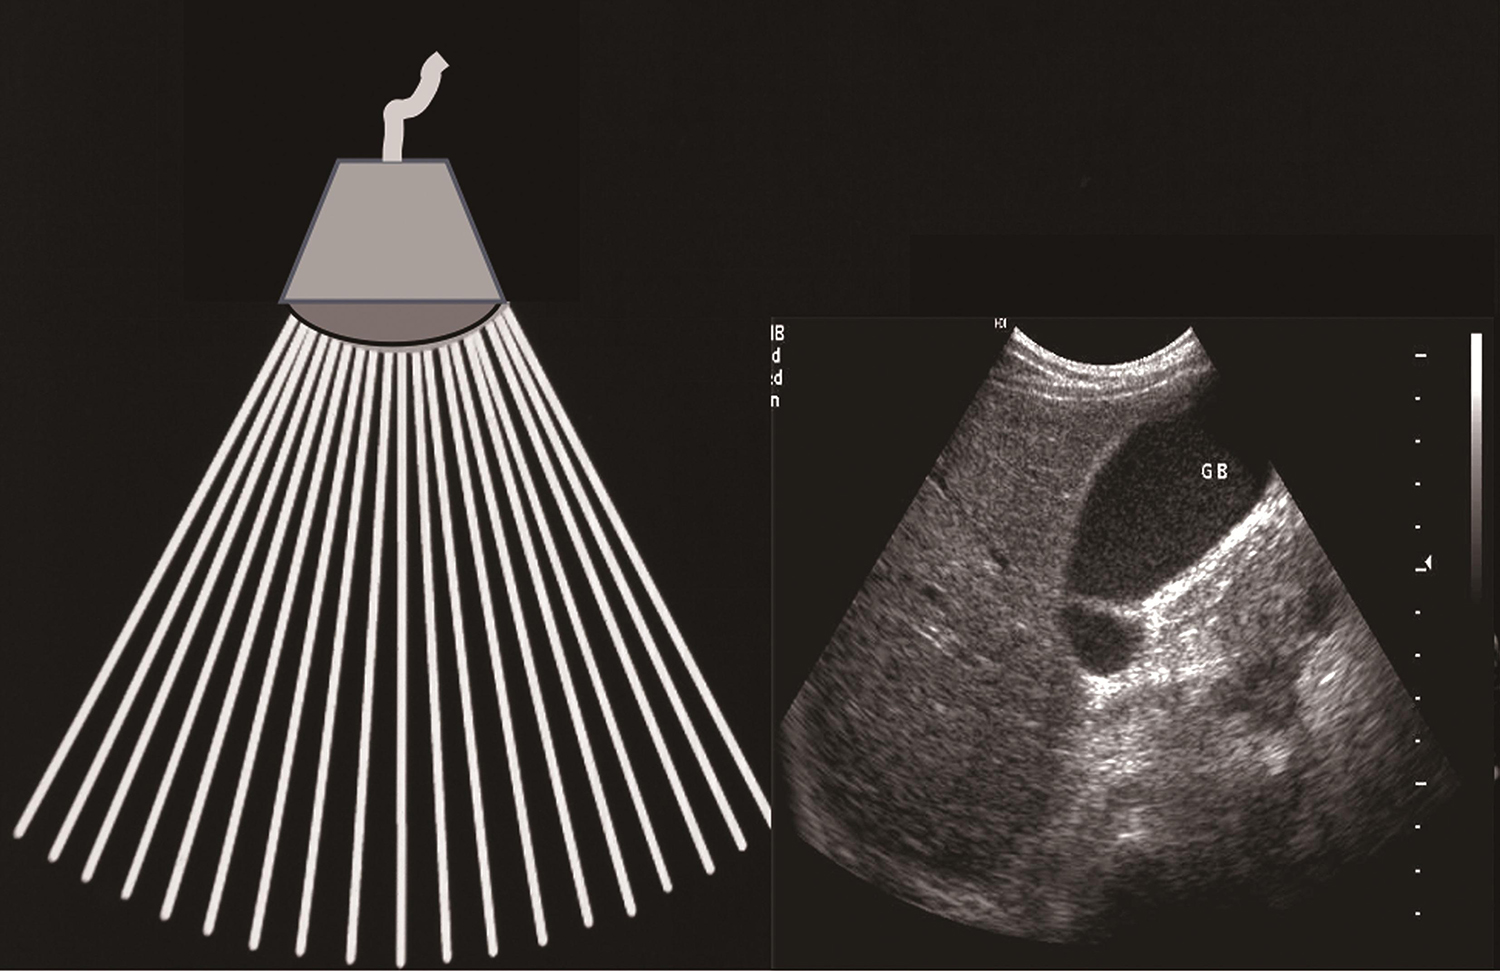

简称“B型法(B-mode)”。将回声强度以不同亮度,即灰阶(grey scale)显示。探头每发射一次声脉冲,组织的回声就连成一条与经过组织深度和强度一一对应的辉度线。单声束进行快速扫查或多声束同时扫描,线动成面,即组成反映组织声学特征的实时二维灰阶图像(图1-1-3-3)。声像图像素点的位置和亮度(辉度)与人体解剖切面的空间位置和声学特征对应。

图1-1-3-3 B型法成像原理

常用扫查方式包括扇形扫描(机械扇扫探头、相控阵和环阵探头)、线形扫描、凸阵扫描。